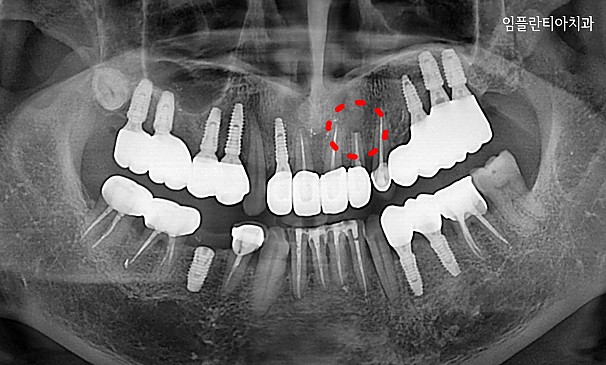

뿌리염증 제거술란?

치아 뿌리 끝에 염증이 생긴 경우는 몇 가지의 원인이 있습니다. 교합문제나 다른 자연 발생적으로 생긴 염증일 수 있고,

이미 신경 치료된 치아가 어떤 이유에서 다시 감염 되었을 때도 뿌리에 염증이 생길 수 있습니다. 염증이 생긴 원인과 염증 범위에 따라 여러 가지 형태로 치료할 수 있습니다.

뿌리염증 제거술